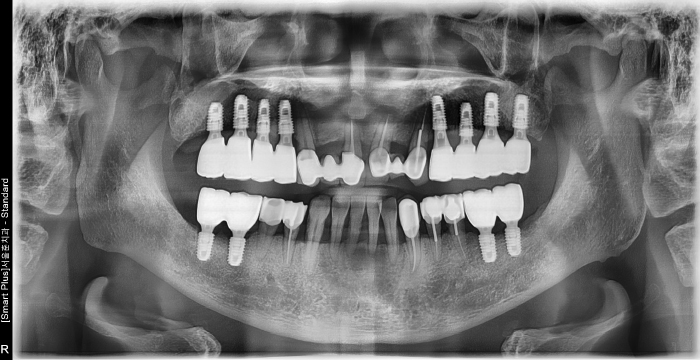

즉시 식립 임플란트 전후 사례

• 식립 전

식립 후

식립 전